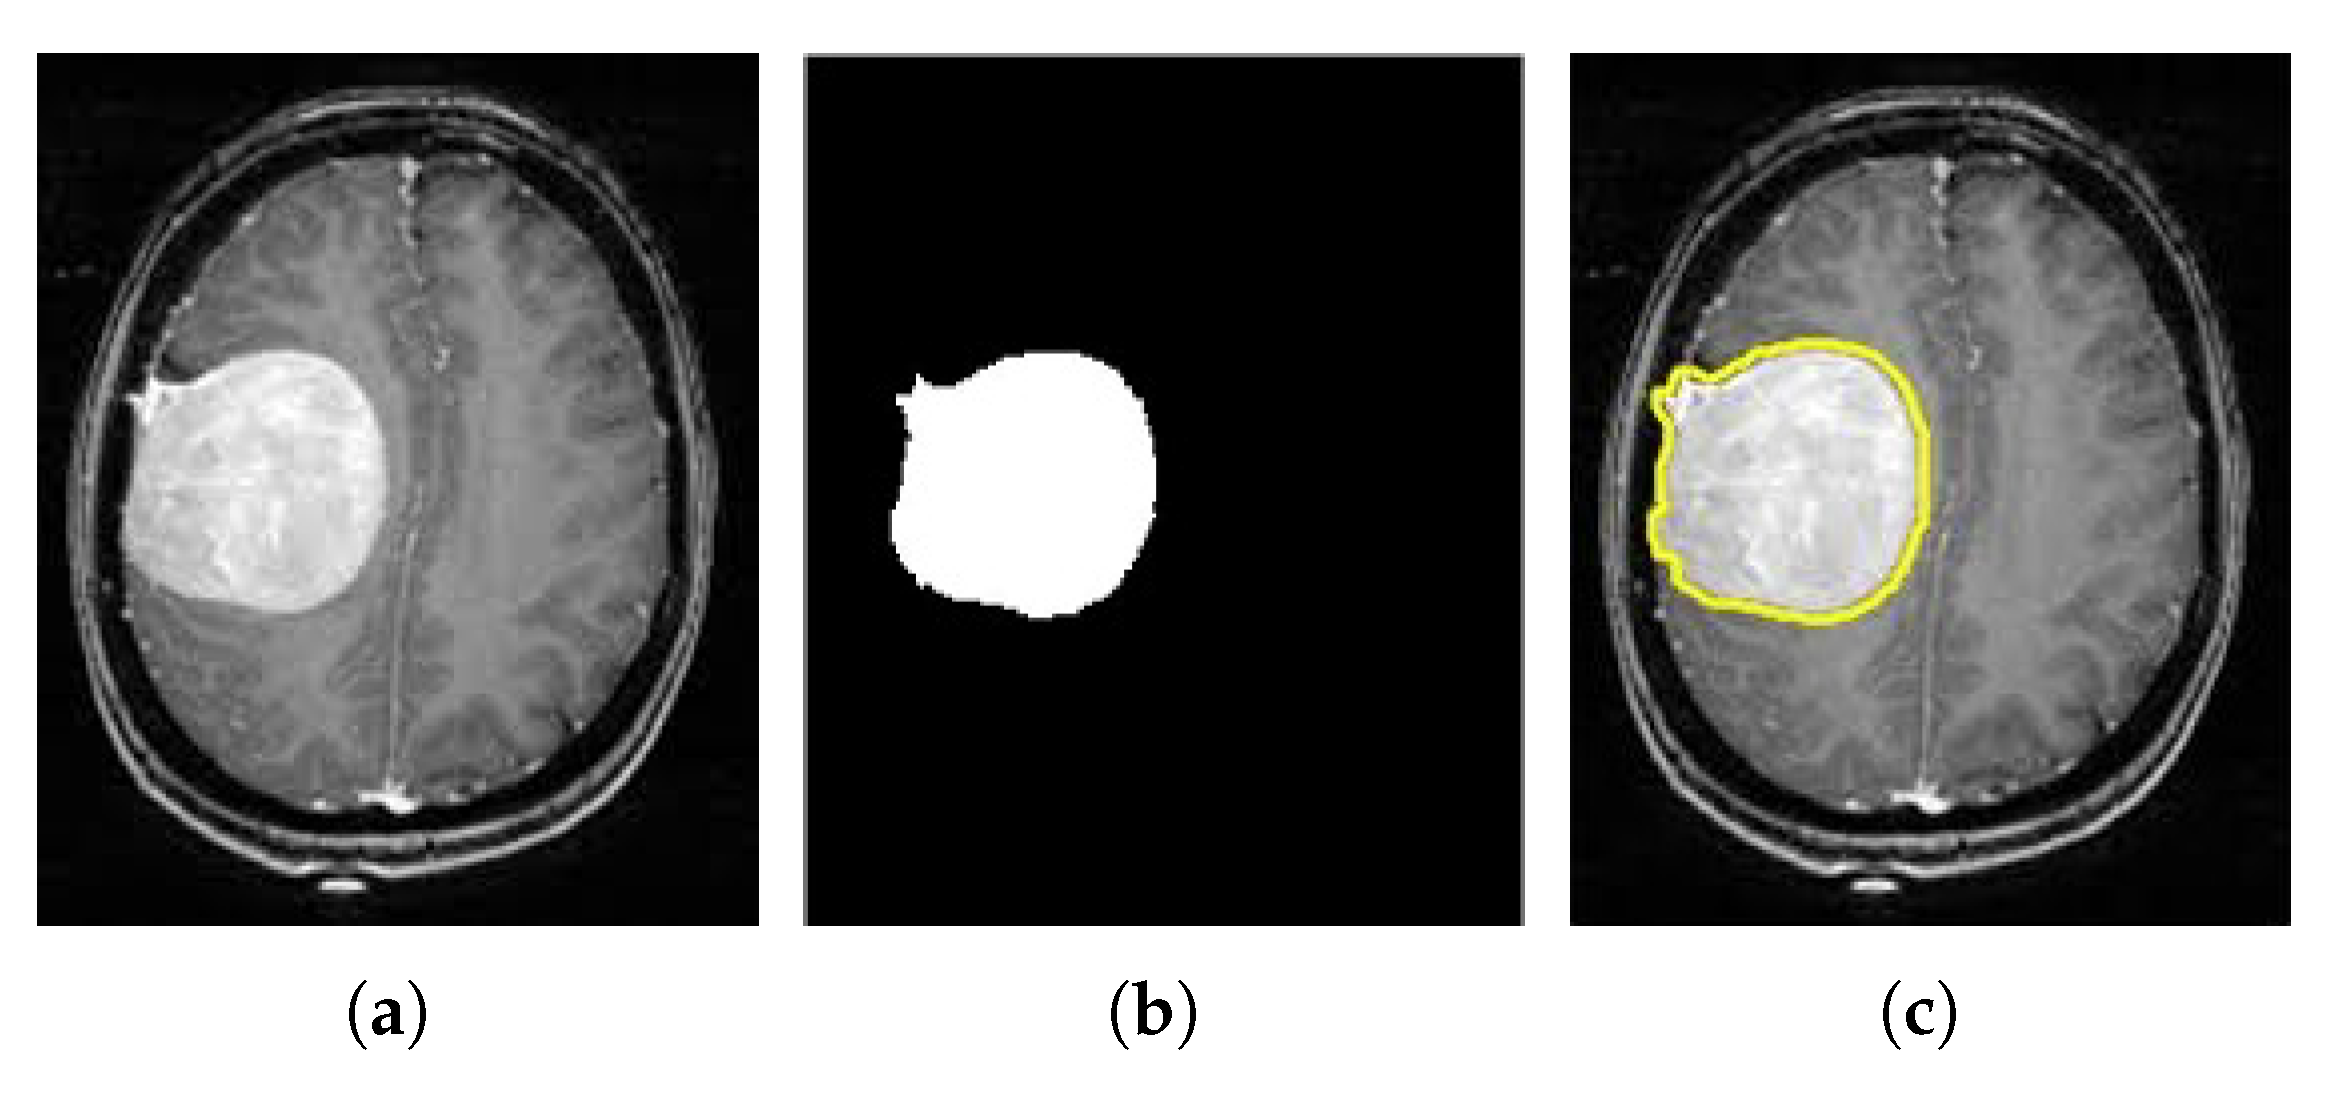

3.2. Tumor Segmentation

5.1. Brain Tumor Segmentation Results